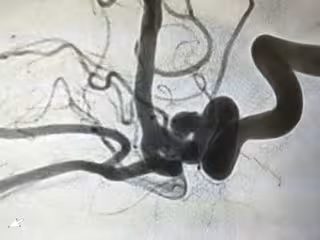

El aneurisma de la aorta abdominal es la dilatación asintomática de la aorta, lo que dificulta su diagnóstico, pudiendo progresar hasta que se produce la rotura de la arteria, dando lugar al 1-2% del total de muertes. En la actualidad no existen tratamientos farmacológicos que ayuden a prevenir su progresión, siendo la intervención quirúrgica, cuando el aneurisma de la aorta abdominal es mayor de 5-5.5 centímetros, la única alternativa terapéutica.